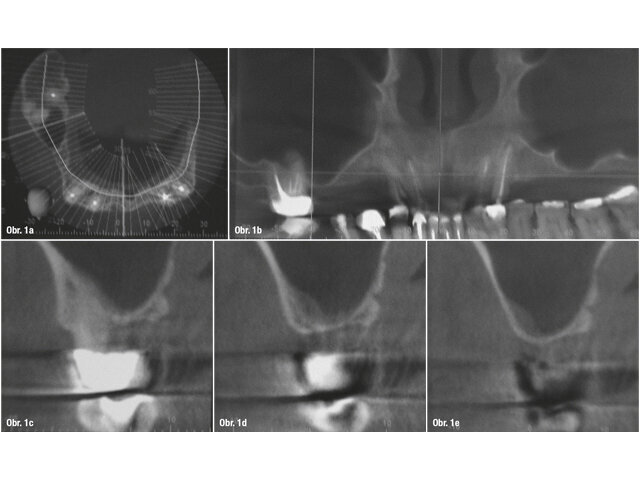

Na naše pracoviště se dostavil dvaapadesátiletý pacient s žádostí o estetickou a funkční rekonstrukci chrupu. Osobní anamnéza byla ze stomatologického pohledu nevýznamná a z anesteziologického hlediska byl pacient klasifikován jako ASA I (zcela zdravý jedinec). Před zahájením ošetření pacient podepsal informovaný souhlas. Na základě radiologického (obr. 1a–e) a klinického (obr. 2a) vyšetření jsme navrhli zavedení implantátů do distálního úseku prvního kvadrantu k náhradě zubů 14, 15 a 16.

Preoperační CT analýza: a) koronální řez zachycující omezenou nabídku vertikální kosti a b) panoramatický pohled na horní čelist se zjevným nedostatkem vertikální reziduální kosti v prvním kvadrantu. c–e) Sagitální řez v oblasti zubu 16 s vertikální nabídkou kosti menší než 1 mm.